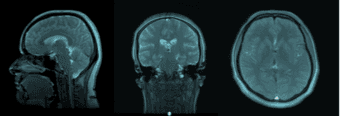

Are you the parent of a healthy 8-17 year old child? Would your child be interested in participating in medical research and taking home a picture of her or his brain?

Parents and their children are needed for a brain-imaging study that explores predictors of emotional resilience in children and adolescents.

The study takes place in the Department of Psychiatry and Behavioral Sciences at Stanford University. You and your child would participate in interviews, your child would do some activities on a computer, and even have a noninvasive MRI scan taken of his/her brain.